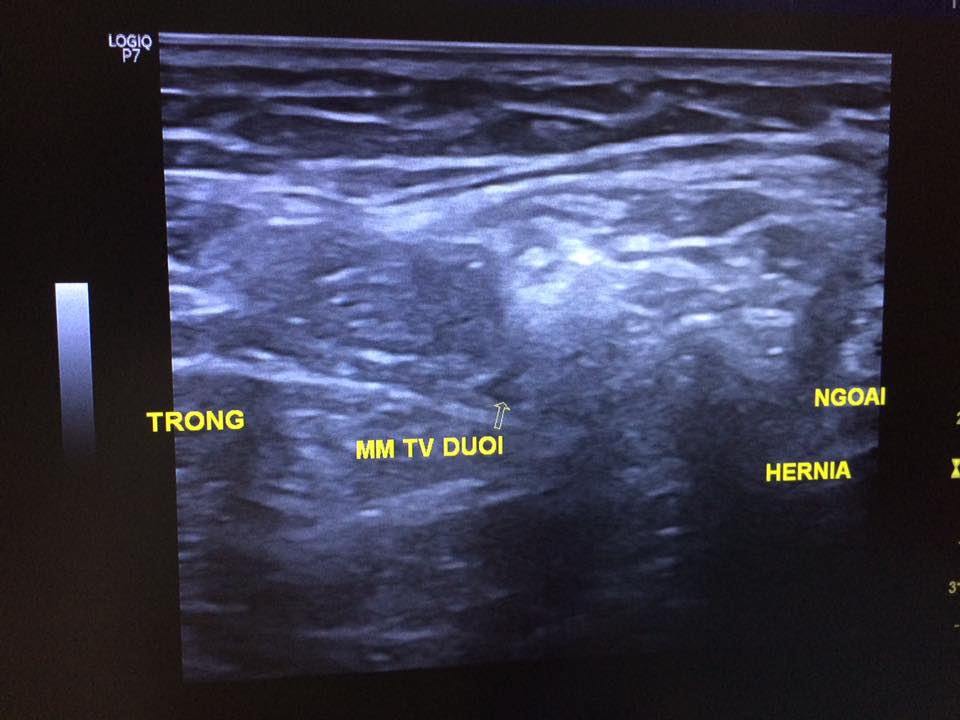

Staff member 4. Nam 67t Ls: chuẩn bị mổ thoát vị ben t => bs pt muốn sa lại trước pt Clip sa bẹn trái Chẩn đoán? 14908238_565556773642431_7094452599200745576_n.jpg 14900543_565556830309092_6731208493409609365_n.jpg 14963305_565556790309096_4643616292348455768_n.jpg 14908193_565556873642421_859291706916583555_n.jpg 14900519_565556826975759_1726480362463028455_n.jpg Nguồn: Code: https://www.facebook.com/groups/cdhaOnline/permalink/780379048767244/ Spoiler: Đáp án: Thoát vị, chưa thấy bc nghẹt... Vị trí: cổ túi thoát vị phía NGOÀI BÓ MẠCH THƯỢNG VỊ DƯỚI VÀ PHÍA TRÊN DC BẸN=> tv gián tiếp (tv giá tiếp còn 1 dh ko quan trọng là túi tv nằm dọc phía nông và ngoài so với bó mạch thừng tinh- như case này) Quan trọng và khó khăn là cắt ra dc bẹn và mm tv dưới -------------------------------------- Video này được chia sẻ với mục đích nâng cao hiểu biết và kinh nghiệm cho cộng đồng những người làm y khoa. Không vì mục đích vụ lợi nào khác. Những mô tả và kết luận bệnh lý trong video này mang tính chất tham khảo và chỉ dành cho những người có chuyên môn. Vui lòng kiểm tra thật kỹ thông tin trước khi áp dụng vào thực tế. Nếu bạn là chủ nhân video và cảm thấy không hài lòng về điều này, hãy liên hệ với chúng tôi: [email protected] You must log in or register to reply here. Share: Facebook Twitter Reddit Pinterest Tumblr WhatsApp Email Share Link